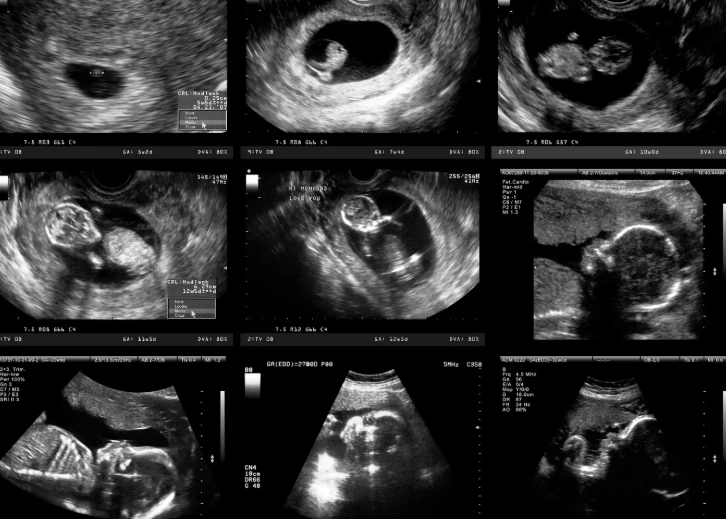

- Movement: Oh, they're moving! Kicking, stretching, even making little fist clenches. You won't feel it for several more weeks, but on an ultrasound, it's a beautiful, wiggly sight.

It's truly astonishing how much is accomplished in this first trimester. The Mayo Clinic provides excellent week-by-week details that reinforce just how dynamic this period is. Seeing this on a screen really drives home the reality of it all.

A: You've likely had initial blood work. The first-trimester screening, which can include a nuchal translucency ultrasound and blood tests (like the combined test), is typically done between weeks 11 and 14. This screens for certain chromosomal conditions. If you haven't discussed this with your provider, now is the time.